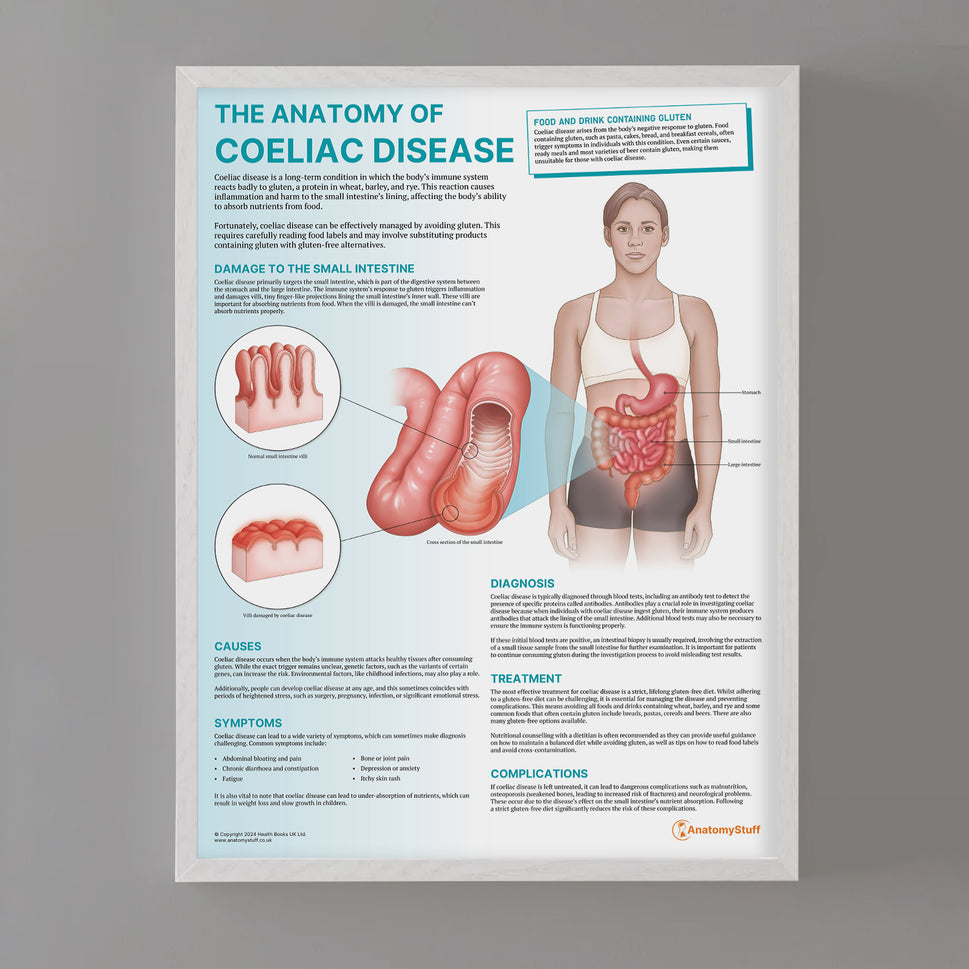

At AnatomyStuff we stock a diverse range of digestive system anatomical models to suit your training needs. From budget models and affordable medical education posters to highly advanced 3D printed bowel models, you can transform medical training and patient education. As well as our own exclusive collection, we are proud resellers of 3B Scientific, Anatomy Lab, Denoyer-Geppert Science Company, ESP Models, Erler Zimmer and GPI Anatomicals. Explore our exclusive collection of digestive system anatomy charts, posters, fine art prints and digital anatomy study guides. Discover the anatomy of key organs like the liver, stomach, pancreas and bowel as well as the pathophysiology of common conditions like peptic ulcer disease, coeliac disease, IBD and much more. We have anatomy posters suitable for school children all the way up to medical degree level. From a liver anatomy poster to a digital study guide all about common GI disorders, find exactly what you need right here to enhance medical training and patient education.